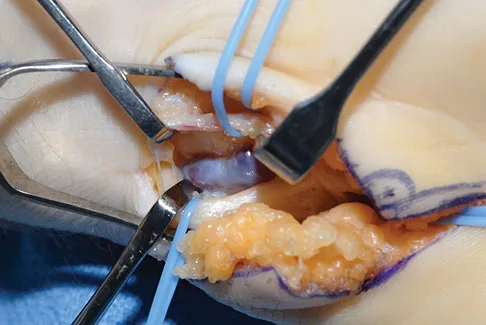

A 65-year-old man has a painful mass of the middle finger. A clinical photograph, lateral radiograph, coronal MRI scan, and biopsy specimen are seen in Figures 20a through 20d. What is the most likely diagnosis?